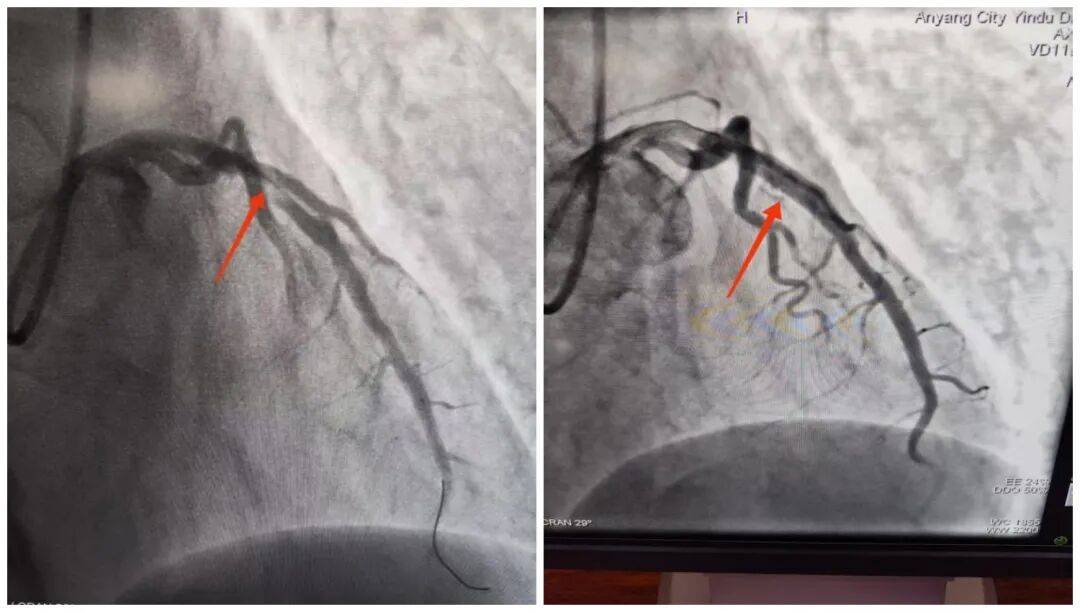

14:54,承载着生命希望的救护车抵达殷都区人民医院大门口。14:56,刘大爷被推至导管室门口,早已等候在此的医护团队立即上前,无缝衔接将刘大爷推进导管室,手术随即开始。15:18,医院介入团队精准操作,治疗导丝成功通过病变部位,血管开通的关键一步顺利完成。15:50,手术圆满结束,成功挽救了濒临坏死的心肌。从刘大爷到达殷都区人民医院门口到成功开通堵塞血管,整个过程仅用了24分钟,这一速度远优于国际通行的90分钟黄金标准。

此次对刘大爷的成功救治,并非偶然,而是“心电一张网”打破诊疗壁垒、实现双院高效联动的生动实践。曲沟卫生院作为基层网络医院,在救治初期快速完成基础检查与初步处置,为后续治疗“打底”;殷都区人民医院专业团队则凭借精湛技术和高效协作,精准“接力”,确保救治方案快速落地、手术顺利推进。两者紧密配合,真正打通了辖区内急性胸痛患者的分级救治绿色通道,为群众的生命健康筑起了一道坚实的“防护墙”。